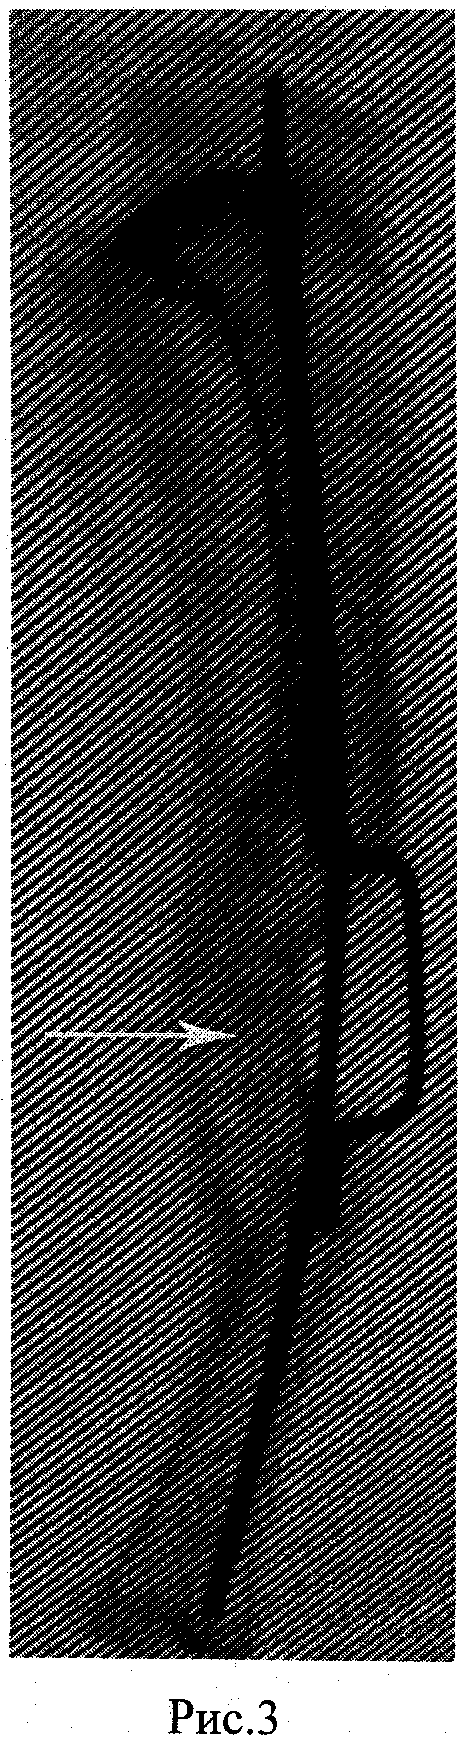

Рис.3. Большеберцовая кость кролика. В центральной части определяется костный регенерат (обозначен белой стрелкой), образованный с помощью композита.